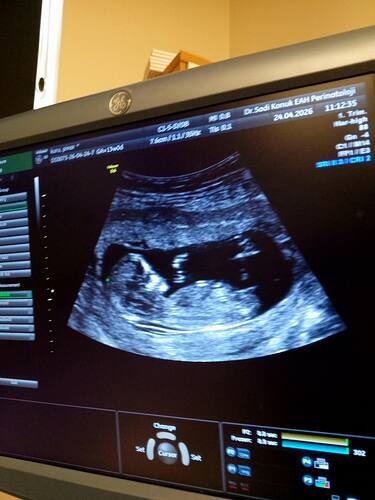

Bu attığımda yeni onada bi bakarmısın cnmm

Erkek bebek gibi duruyor canim

Bu bir prenses gibi duruyor canim